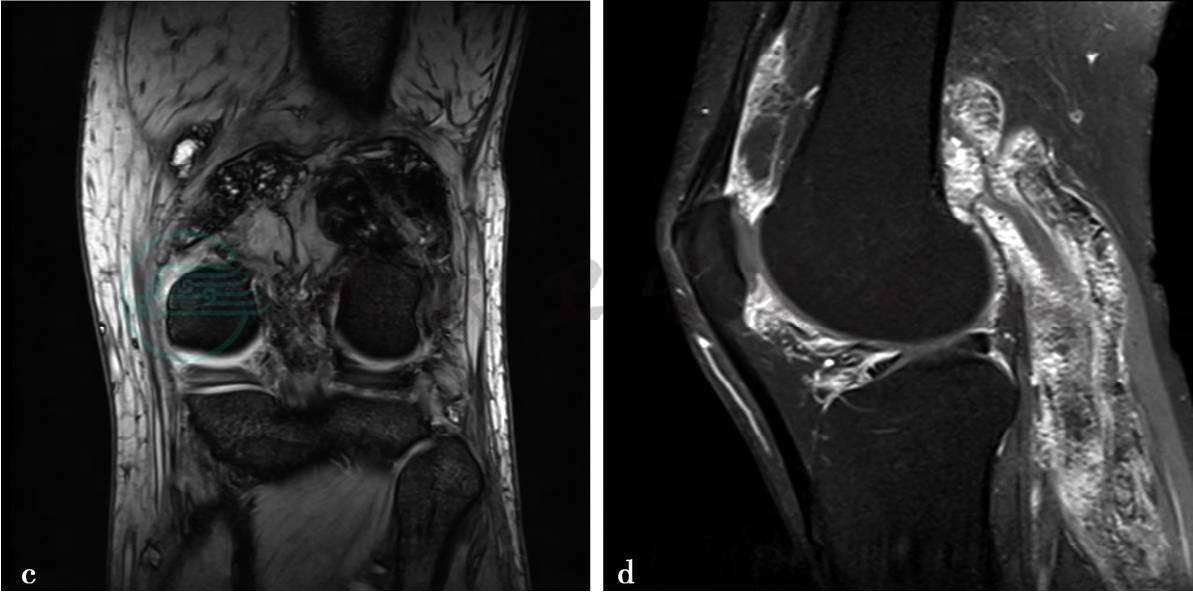

图2 图2a~c,MRI平扫示左股骨远端后方及腘窝软组织内可见多发不规则病灶。图2a,病灶在T1WI上呈低信号。图2b,在T2WI脂肪抑制像上呈高低混杂信号。图2c,MEDIC序列像上呈低信号,边界不清楚。左股骨远端后方异常信号呈类圆形,大小约2.4cm×1.1cm。膝关节后下侧病灶呈长带状,大小约12cm×3.5cm。半月板未见异常。关节囊内可见少量液体信号。图2d,MRI增强扫描示左膝关节滑膜明显增厚强化,上述平扫时显示的膝关节后侧软组织影,呈明显多发结节样强化,其内散在小点状及条形低信号